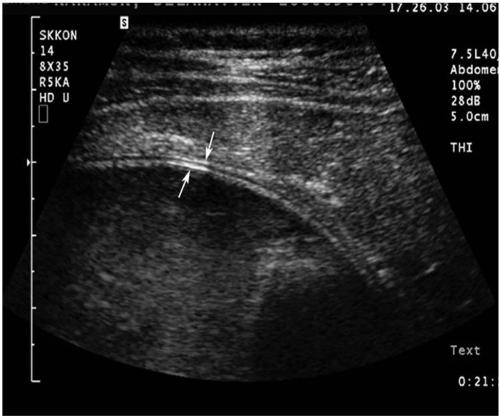

Hydatid disease (HD) is an endemic illness in many countries, and it poses an important public health problem that's influenced by peoples' socioeconomic status and migration that spreads this disease. Although rare, it may occur in any organ or tissue. The most common site is the liver (59-75%), followed in frequency by lung (27%), kidney (3%), bone (1-4%) and brain (1-2%). Other sites such as the heart, spleen, pancreas and muscles are very rarely affected. Unusual sites for this disease can cause diagnostic problems. This pictorial essay illustrates various radiological findings of HD in the liver, spleen, kidney, pancreas, peritoneal cavity, omentum, adrenal, ovary, lung, mediastinum and retroperitoneum. Familiarity with the imaging findings of HD may be helpful in making an accurate diagnosis and preventing potential complications.